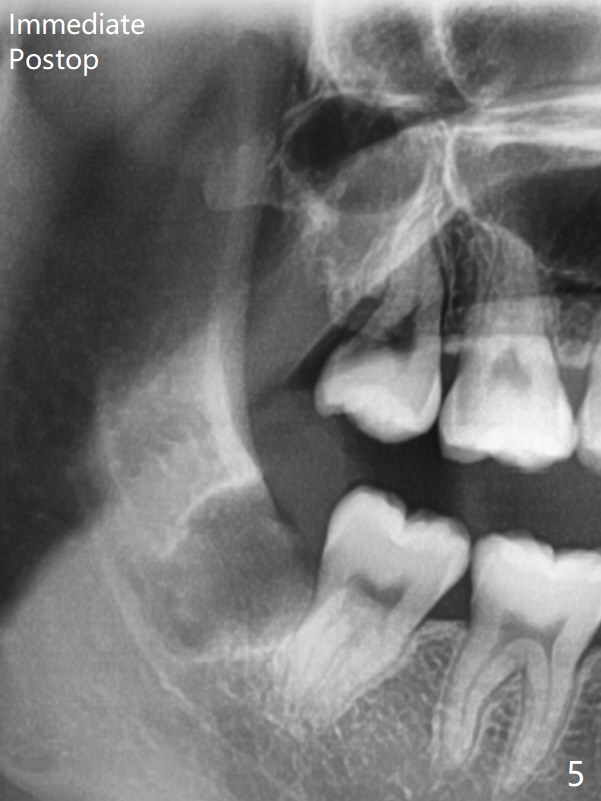

A 22-year-old man will return for 3rd molar extraction (4 of them, Fig.1-4). Prepare 2 or 3 #15 blades and 1-2 extra surgical burs. Since the third molars may overlap with the second ones, oblique incision (red line in Fig.4') will be mesial. Place Collagen and Osteogen plugs in the #32 and 17 sockets, respectively (Fig.4': C, O). As the roots are short and bone formation distal to the 2nd molars is critical, the plugs will be placed horizontally and coronally (Fig.4' white outline). No dovetail is needed. Pan 4 BW will be taken immediately and 3-4 months postop. The experiment will confirm whether collagen plug is enough to facilitate socket bone healing. In fact extraction of #1 turns out to be extremely difficult. There is not enough time for #16 and 17 extraction in one appointment (Fig.5).